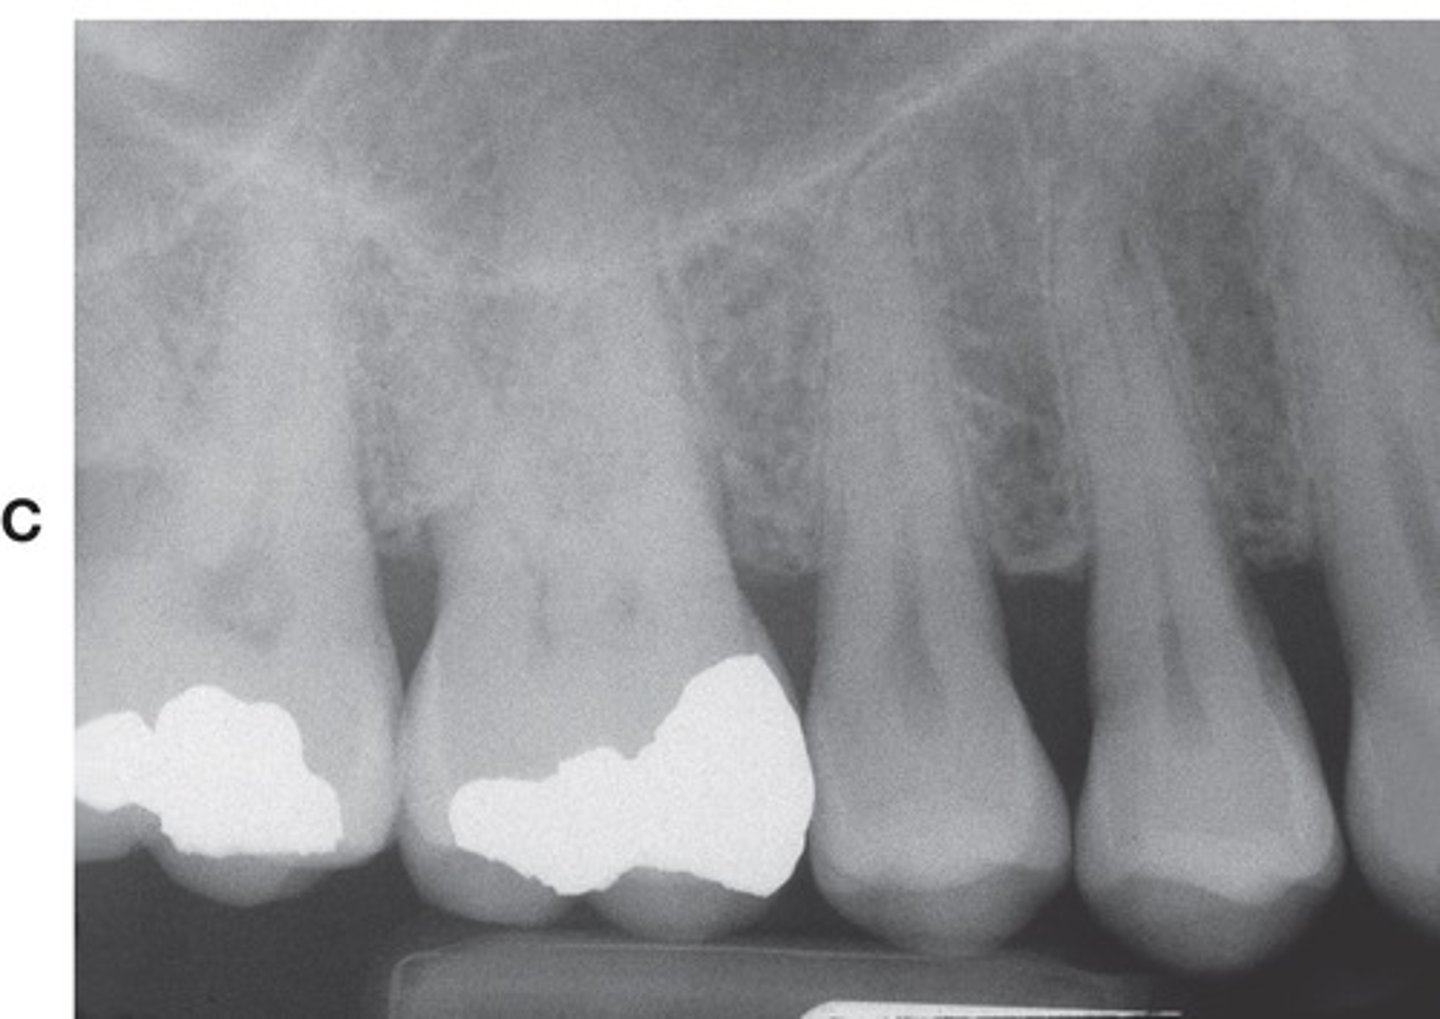

Example of a periapical x-ray:

How many teeth does periapical imaging usually display?

- two to four teeth.

What anatomy is demonstrated in periapical imaging? What kind of information?

• Provides detailed information about the teeth and the surrounding alveolar bone

• Demonstrates crown to apex.

• At least 2mm bone, ideally 5mm beyond apex.